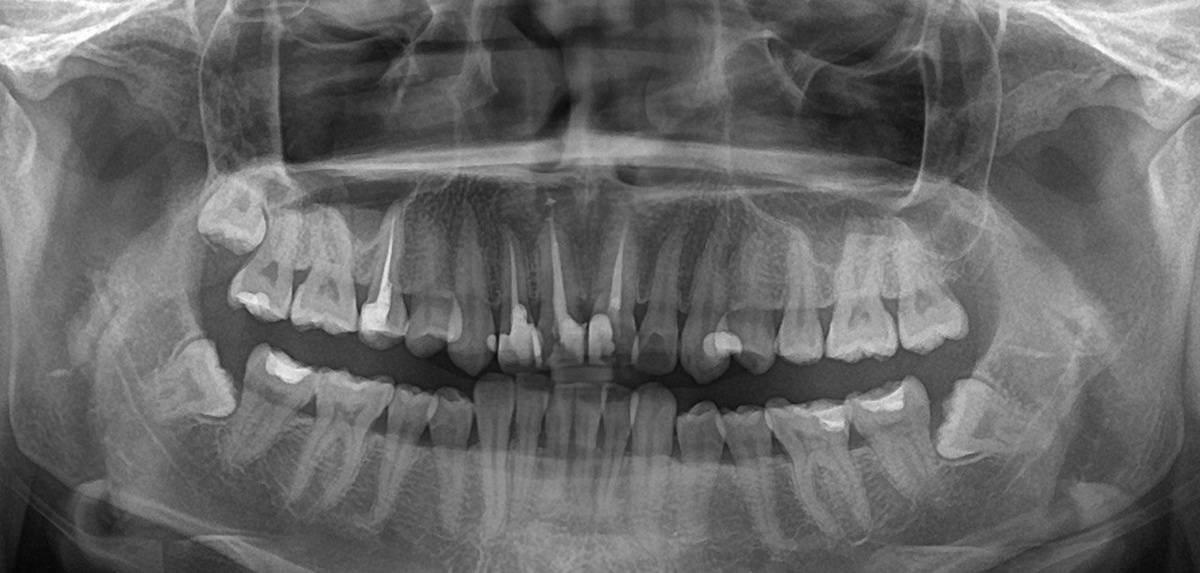

Шаг 1 – диагностические снимки

Я бы даже рекомендовала сделать это до консультации с врачом ортодонтом. Наличие снимков уже не первой консультации (панорамный, ТРГ, КТ), поможет ортодонту провести более точную диагностику и составить детальный план лечения. Эти же снимки помогут вам в дальнейшей подготовке.